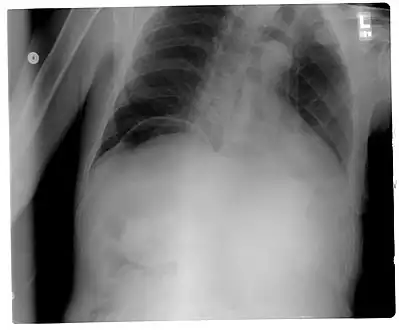

Another pneumoperitoneum on chest X-ray.

When present, pneumoperitoneum can be seen on projectional radiography, but small amounts are often missed, and CT scan is nowadays regarded as a criterion standard in the assessment of a pneumoperitoneum.[18] CT can visualize quantities as small as 5 cm3 of air or gas.

Signs that can be seen on projectional radiography are shown below: